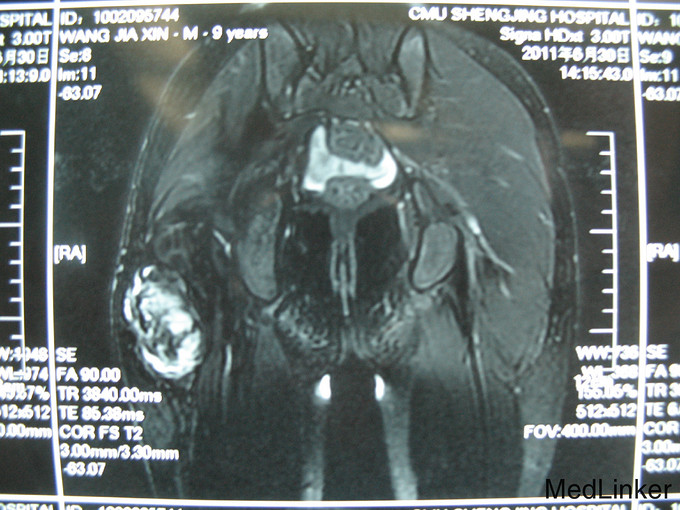

右臀部手术区可见15cm长的手术瘢痕,瘢痕下可 及硬韧肿物大小约10x7cm,边界不清,活动度差。

侵袭性纤维瘤病是一种不明原因、不发生转移的成纤维细胞性瘤样肿物。起源于肢体和韧带的肌筋膜结构,累及骨骼肌腱膜和筋膜,并对周围组织产生压迫。病变很易局部复发,并呈侵袭性生长,最常见于青年人的肩胛带、股部及臀部。侵袭性纤维瘤术后复发几率高,对周围组织侵袭性强。本例患者给予扩大切除术后随诊至今未发现复发病灶。